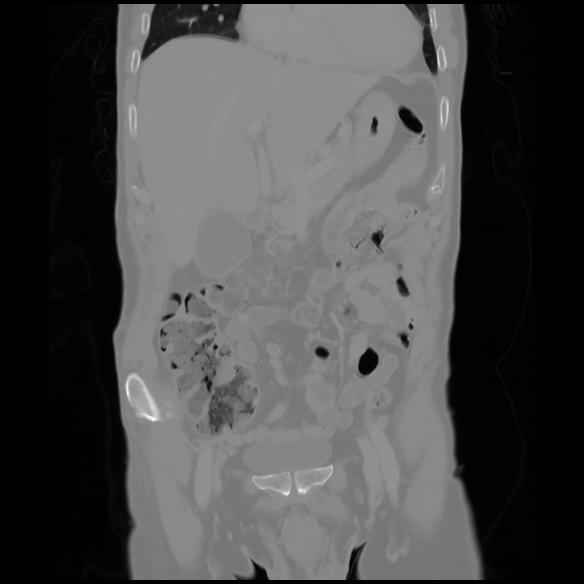

6 CUERPO,CE,Coronal,3.000,CUERPO,Coronal,